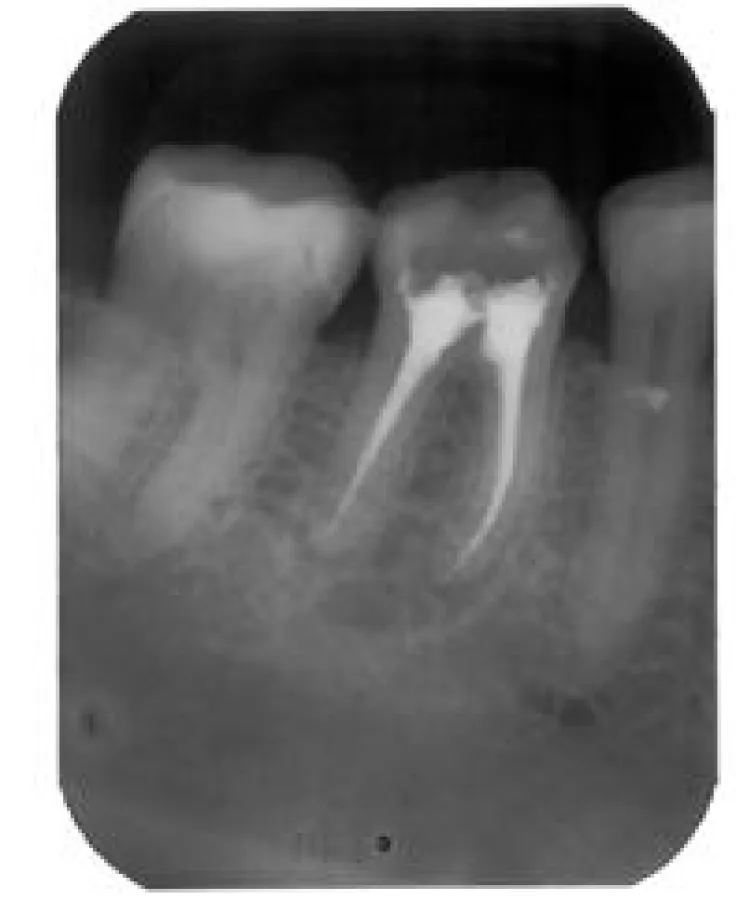

Bild: Gesund bis in die Wurzel – moderne Verfahren machen es möglich

(openPR) Zahnwurzelbehandlung: das Wort allein klingt schon schmerzhaft. Viele Menschen haben Angst eine solche Behandlung vom Zahnarzt vornehmen zu lassen. Doch die Mühe lohnt sich. Denn der Zahnerhalt durch eine Zahnwurzelbehandlung ist einem sonst notwendigen Zahnersatz meist vorzuziehen.

Eine Zahnwurzelbehandlung ist nötig, wenn Karies bis zum Zahnmark der Wurzel vordringt, und so den Weg für gefährliche Bakterien freimacht. Die empfindlichen Nerven und Gefäße im Zahninneren werden von diesen Bakterien infiziert und entzünden sich. Dank modernster Geräte und technischer Innovationen lassen sich die Entzündungsherde heute jedoch mit großem Erfolg entfernen. Der Zahn wird aufgebohrt, um das infizierte Gewebe und die Bakterien aus dem Wurzelkanalsystem zu entfernen. Zum Abschluss der Wurzelbehandlung wird der gereinigte Zahn versiegelt. So kann er bei optimaler Versorgung ein Leben lang erhalten bleiben.